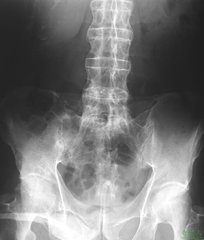

强直性脊柱炎诊断

一般的患者伴有腰痛、腰僵等症状,一般这种症状持续3个月以上,经过休息不能缓解,还有就是单侧,或双侧的坐骨神经痛、反复发作的膝关节,或踝关节肿痛,并且没有明显的外伤史和扭伤史。以下五点更有助于确定: